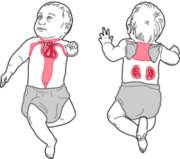

| 12:09, 23 ноября 2015 | Brown adipose tissue4.jpg (файл) |  |

74 КБ | Nico | Бурый жир | 1 |

| 12:07, 23 ноября 2015 | Brown adipose tissue3.jpg (файл) |  |

40 КБ | Nico | Бурый жир | 1 |

| 12:07, 23 ноября 2015 | Brown adipose tissue2.png (файл) |  |

44 КБ | Nico | Бурый жир | 1 |

| 14:13, 22 ноября 2015 | Brown adipose tissue1.png (файл) |  |

96 КБ | Nico | Бурый жир | 1 |